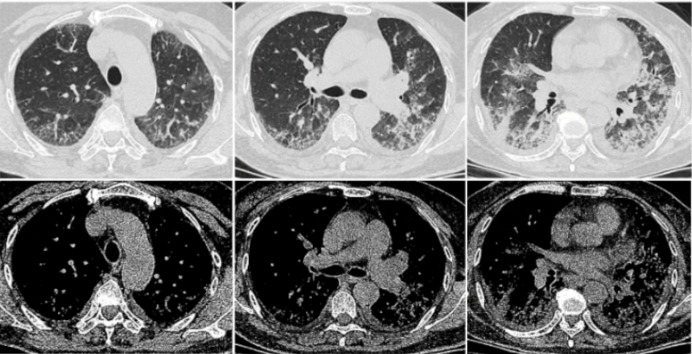

• 胸部CT: 双肺间质性炎症, 胸腔积液(图3)

图片

3  入院胸部CT(2023-11-06)

2023年11月10日HRCT:双肺间质性炎症较前(11月6日)略加重,双侧胸腔积液(图4)

4  复查胸部CT(2023-11-10)